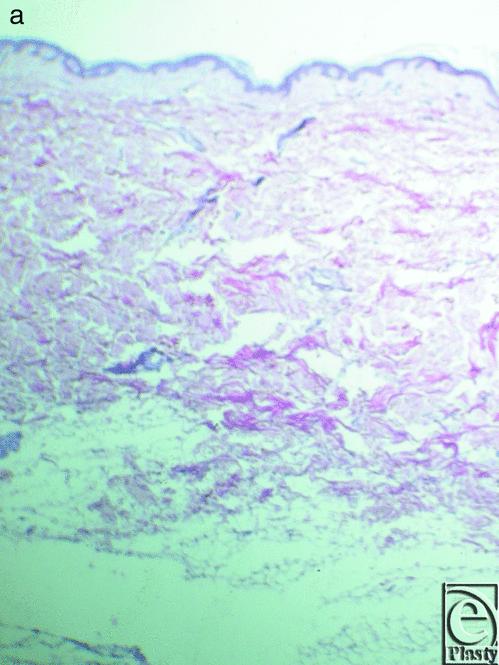

The skin specimens superior and inferior to the skin creases assert that collagen and elastic fibers have a rather random pattern compared with the well-organized network of the fibroelastic bundles in the skin of the creases sites. The elastic fibers are fewer and have a parallel pattern in the dermis (Fig 12a) in the skin inferior and superior to the infragluteal crease and are fewer in number and placed in a parallel pattern in the dermis (Fig 12b) in the skin superior and inferior to the inframammary crease.

In specimens of the skin superior and inferior to the infragluteal crease, the elastic fibers are fewer and orientated parallel to the dermis.

Creases of the trunk are formed by well-organized collagen bundles in a beehive pattern, attached to the dermis and related to the underlying muscle fascia. The anterior axillary fold has less organized collagen bundles and elastic fiber participation and orientation. The elastic fibers participate in the formation of the collagen network and radiate in a parallel fashion in the reticular dermis and in a perpendicular pattern in the papillary dermis. The skin superior and inferior to the creases lacks such organization of the collagen and elastic fibers and is deposited in a random pattern.